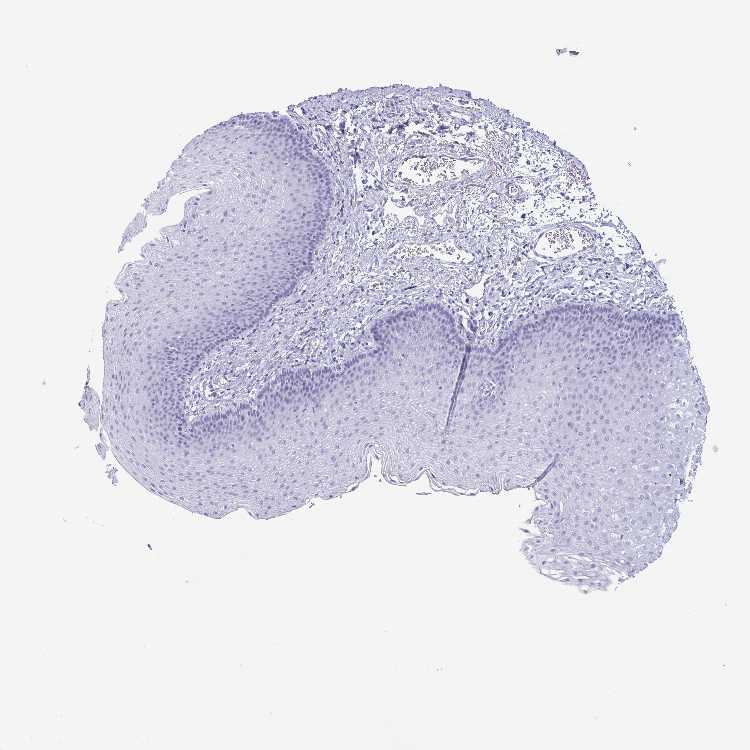

ESOPHAGUS - Antibody stainingi

Antibody staining in the annotated cell types in the current human tissue is reported as not detected, low, medium, or high, based on conventional immunohistochemistry profiling in selected tissues. This score is based on the combination of the staining intensity and fraction of stained cells.

Each image is clickable and will lead to virtual microscopy that enables deeper exploration of all samples and also displays staining intensity scores, fraction scores and subcellular localization as well as patient and tissue information for each sample.

Antibody HPA029299

Squamous epithelial cells Not detected